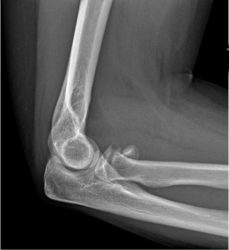

1a. Displaced, multifragmentary fracture of the radial head

A rotation of the displaced, multifragmentary fracture